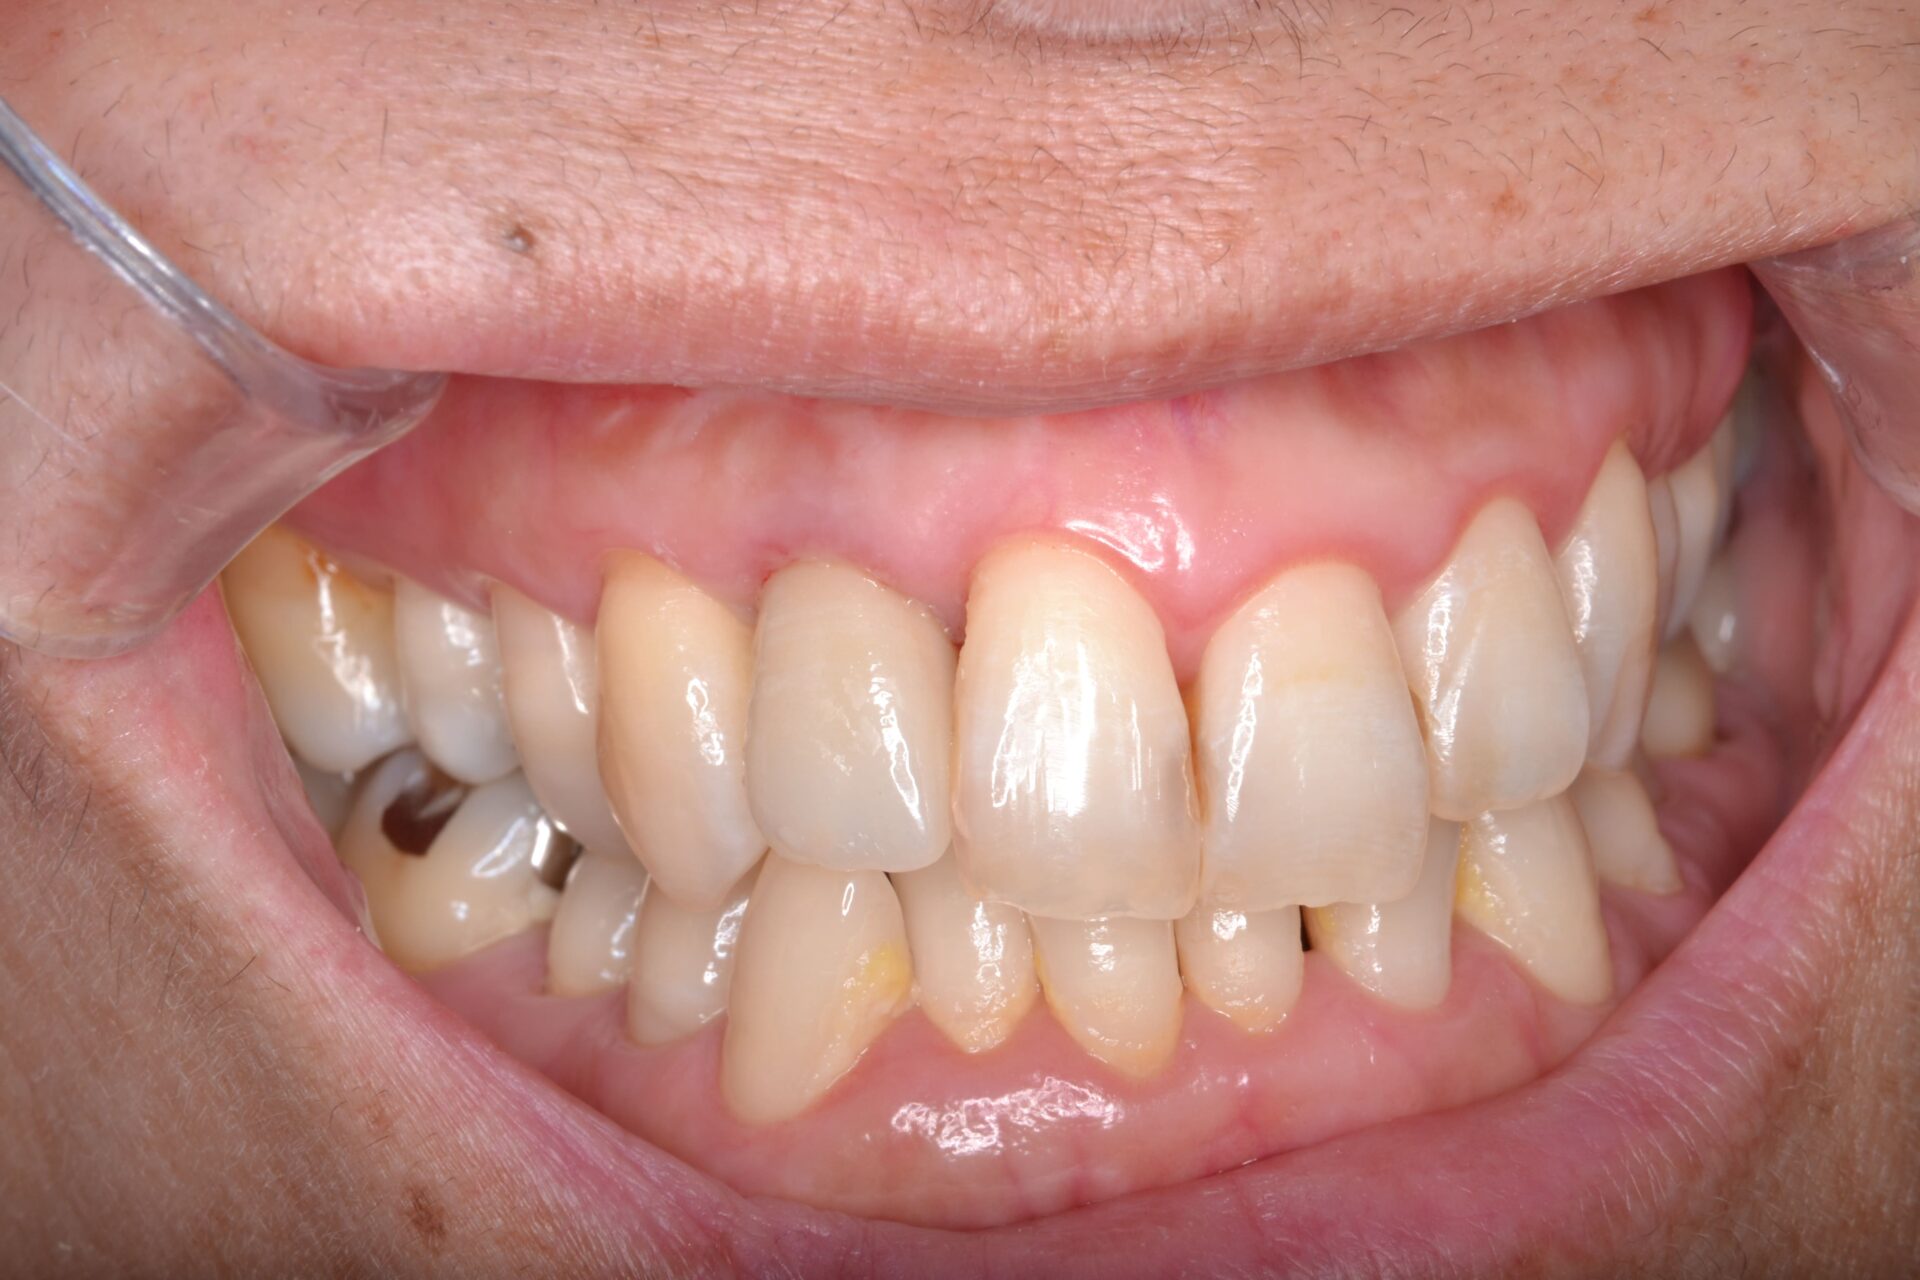

60代 男性

右下の6番目の歯の痛みを訴えられお見えになりました。根が2本あり手前側の根が割れており保存不可能な状態でした。

通常だと抜歯を行いインプラント治療もしくは隣の歯を削ってブリッジですが今回は奥の根だけ残して被せ物を行いました。問題なく噛めており術後2年経過良好です。

費用 | 100000円 |

治療期間 | 6か月 |